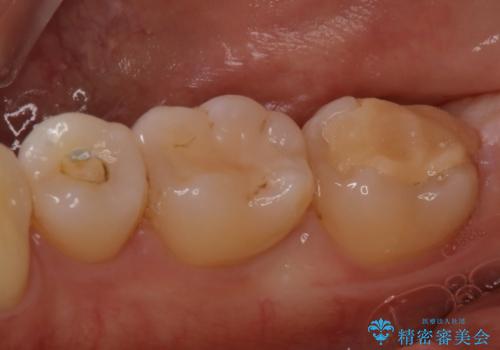

- 昔に治療した金属のかぶせものが取れてしまい来院されました。他院にて応急処置がされており、レントゲンなどで現状を把握した後、切削量が比較的少なく短期間で終了するセラミックアンレーにて治療いたしました。

経過良好で噛み合わせなども問題なく、前の被せ物より綺麗な被せ物がセットされ、非常に満足いただけました。